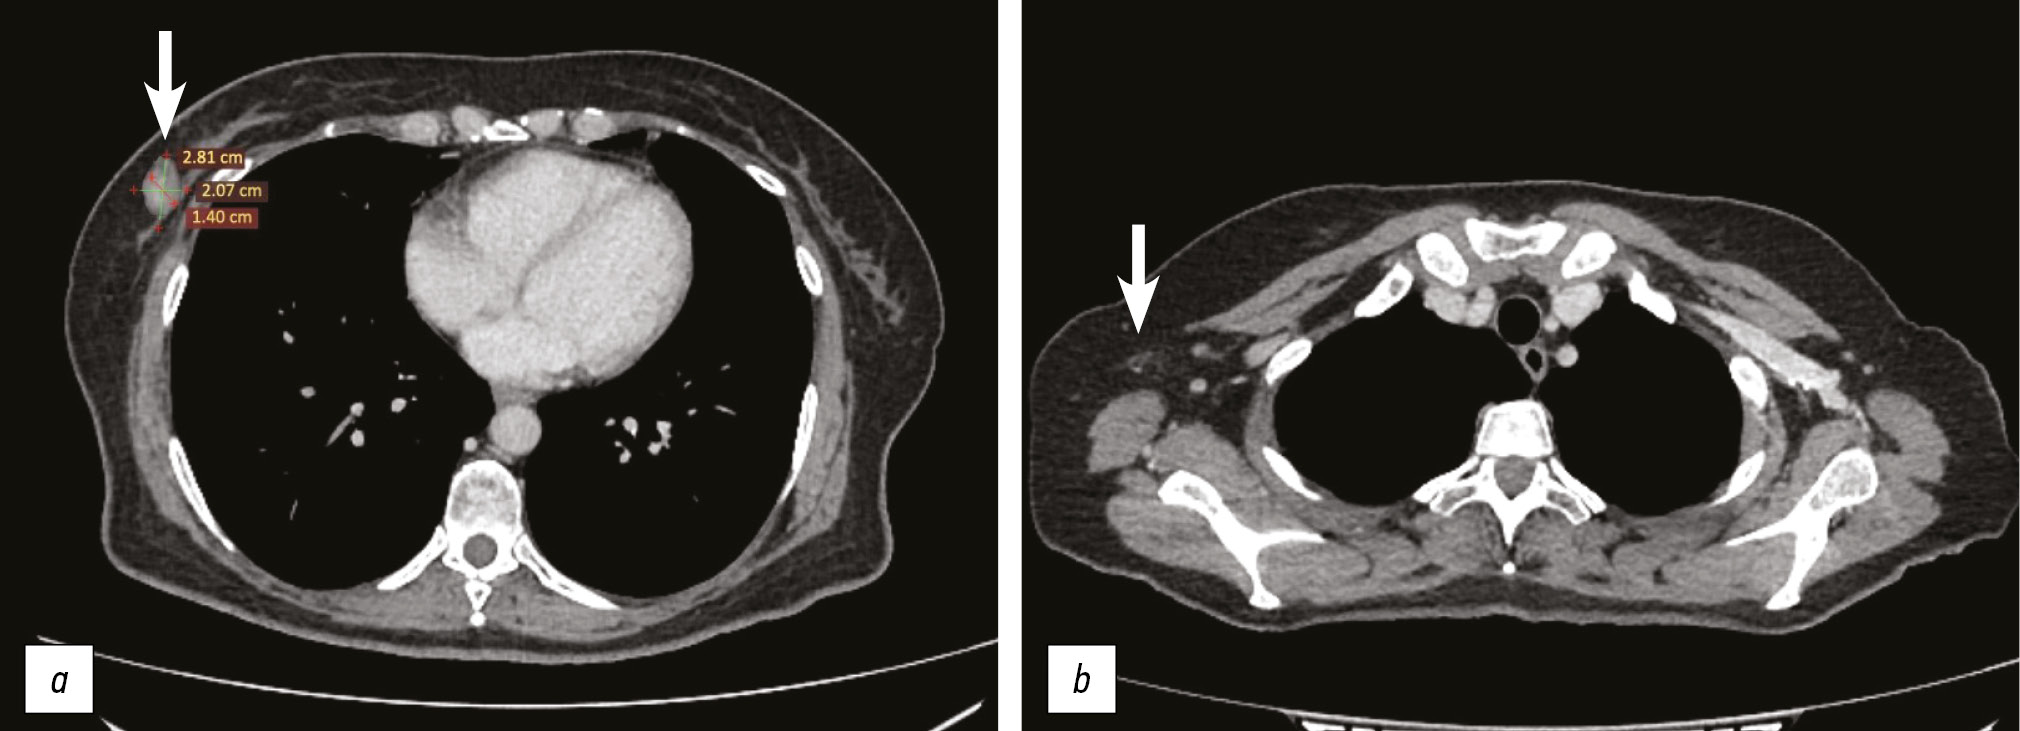

On December 2, 2022, Multislice CT of the chest was performed. No additional lesions in the lungs or mediastinum were detected. In the lower outer quadrant of the right breast, an irregularly shaped mass measuring 28 × 20 × 14 mm was identified. On the right, two enlarged axillary lymph nodes were visible, measuring 15 mm and 6 mm along the short axis (Fig. 1a, b). SoD was 43 mm.

Fig. 1. Computed tomography of the chest from dated December 2, 2022. In the lower-outer quadrant of the right mammary gland, a 28×20×14 mm irregularly shaped formation is identified (a). Two enlarged lymph nodes are identified in the right axillary region (b).